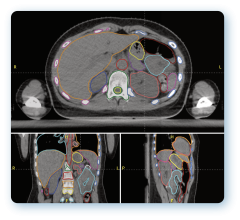

Oct. 3, 2024 — GE HealthCare’s MIM Software has announced it received 510(k) clearance from the U.S. Food and Drug ...

Sept. 30, 2024 – A recent study accepted by the American Society of Radiation Oncology (ASTRO) for their annual meeting ...

Oct. 1, 2024 — At ASTRO 2024, Jay Detsky, MD, PhD, radiation oncologist at Sunnybrook Health Sciences Centre (Toronto ...